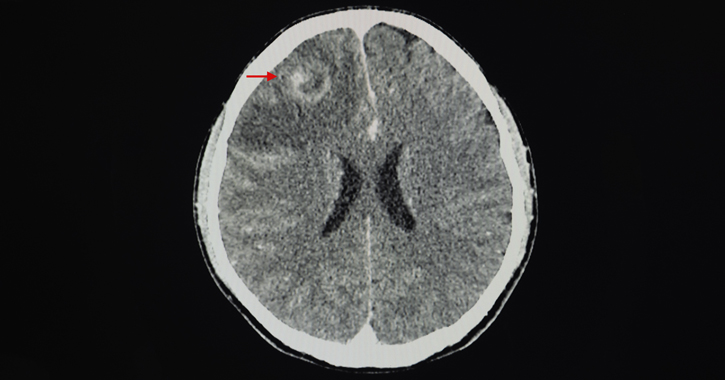

A natív sorozat után, a kontrasztanyag befecskendezését követően az elsőhöz hasonló kontrasztanyagos sorozat készül. Akkor alkalmazzák, ha a natív sorozaton az agyállományban daganat vagy gyulladásos elváltozás, pl. agytályog gyanúja merül fel, illetve ilyen elváltozások kimutatása vagy kizárása a cél. Mivel a kontrasztanyagnak át kell jutni az úgynevezett vér-agy gáton, a sorozat a beadás után 3-5 perces késleltetéssel készül. A daganatok számos típusa, valamint a tályogok fala a kontrasztanyagot felveszi (halmozza), ezáltal jobban elkülönül a környezettől, mint a natív felvételen (lásd alább az 1. képet).

1. kép: A kép bal oldalán a nyíl a homloklebeny daganatára mutat, mely főleg a szélében halmozza a kontrasztanyagot (megjegyezzük, hogy egy tályog is hasonlóan nézhet ki). Az elváltozás körüli sötétebb terület helyi duzzadást, ödémát jelez, ami agyi térfoglaló folyamatok esetén gyakori.